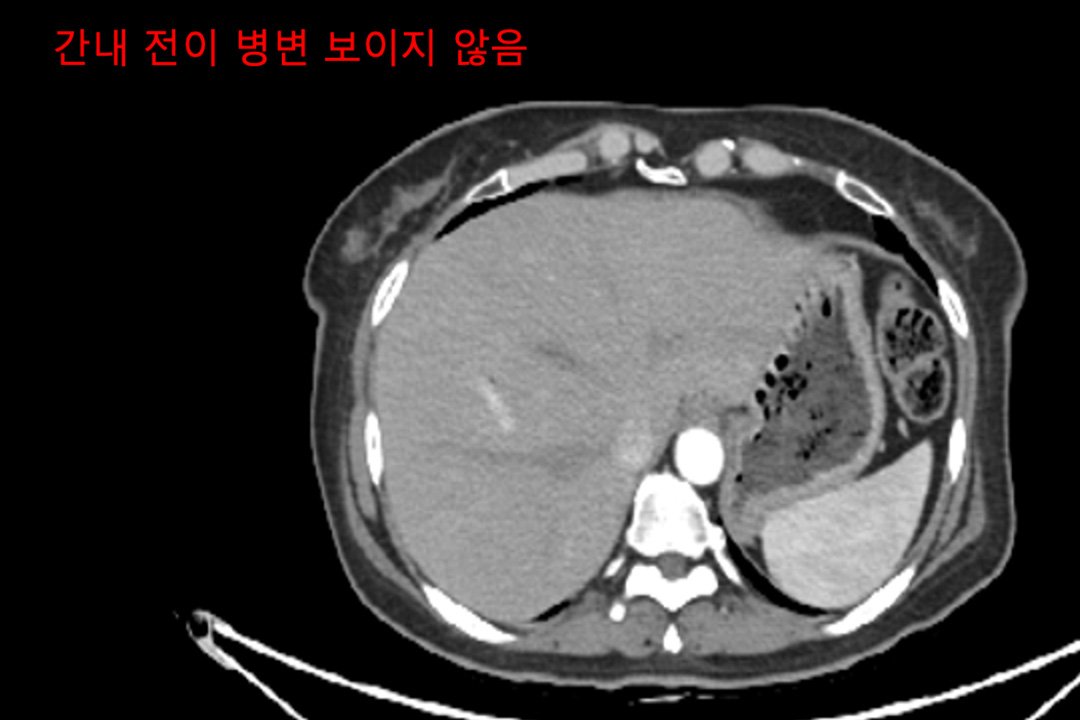

Case of treatment

아미랑에서 치료하신 분들의 소중한 치료사례를 담았습니다.